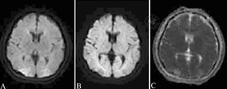

病例3:女性,18岁,因"G1P0孕40周"入院。产后大出血,行子宫动脉栓塞术2 h后出现皮质盲、癫痫发作和烦躁不安,查体:血压162/102 mmHg,嗜睡状态,双侧瞳孔等大等圆,直径2.5 mm,对光反射灵敏,眼底正常,双目可觉轻微光感,四肢肌力正常,脑膜刺激征阴性,病理反射未引出。头颅MRI示双侧顶枕叶片样信号异常,T1低信号、T2及FLAIR高信号、DWI低信号、ADC稍高信号(图3)。考虑注射对比剂引起PRES,给予脱水降颅压、控制血压、止痫、预防脑出血治疗后,未再发抽搐,视力恢复出院。

患者女性,18岁,因"G1P0孕40周"入院,产后大出血,行子宫动脉栓塞术后出现双目失明和癫痫发作,头颅MRI示双侧顶枕叶片样异常信号,液体衰减反转恢复序列呈高信号(A),弥散加权成像呈低信号(B),表观弥散系数图呈稍高信号(C)